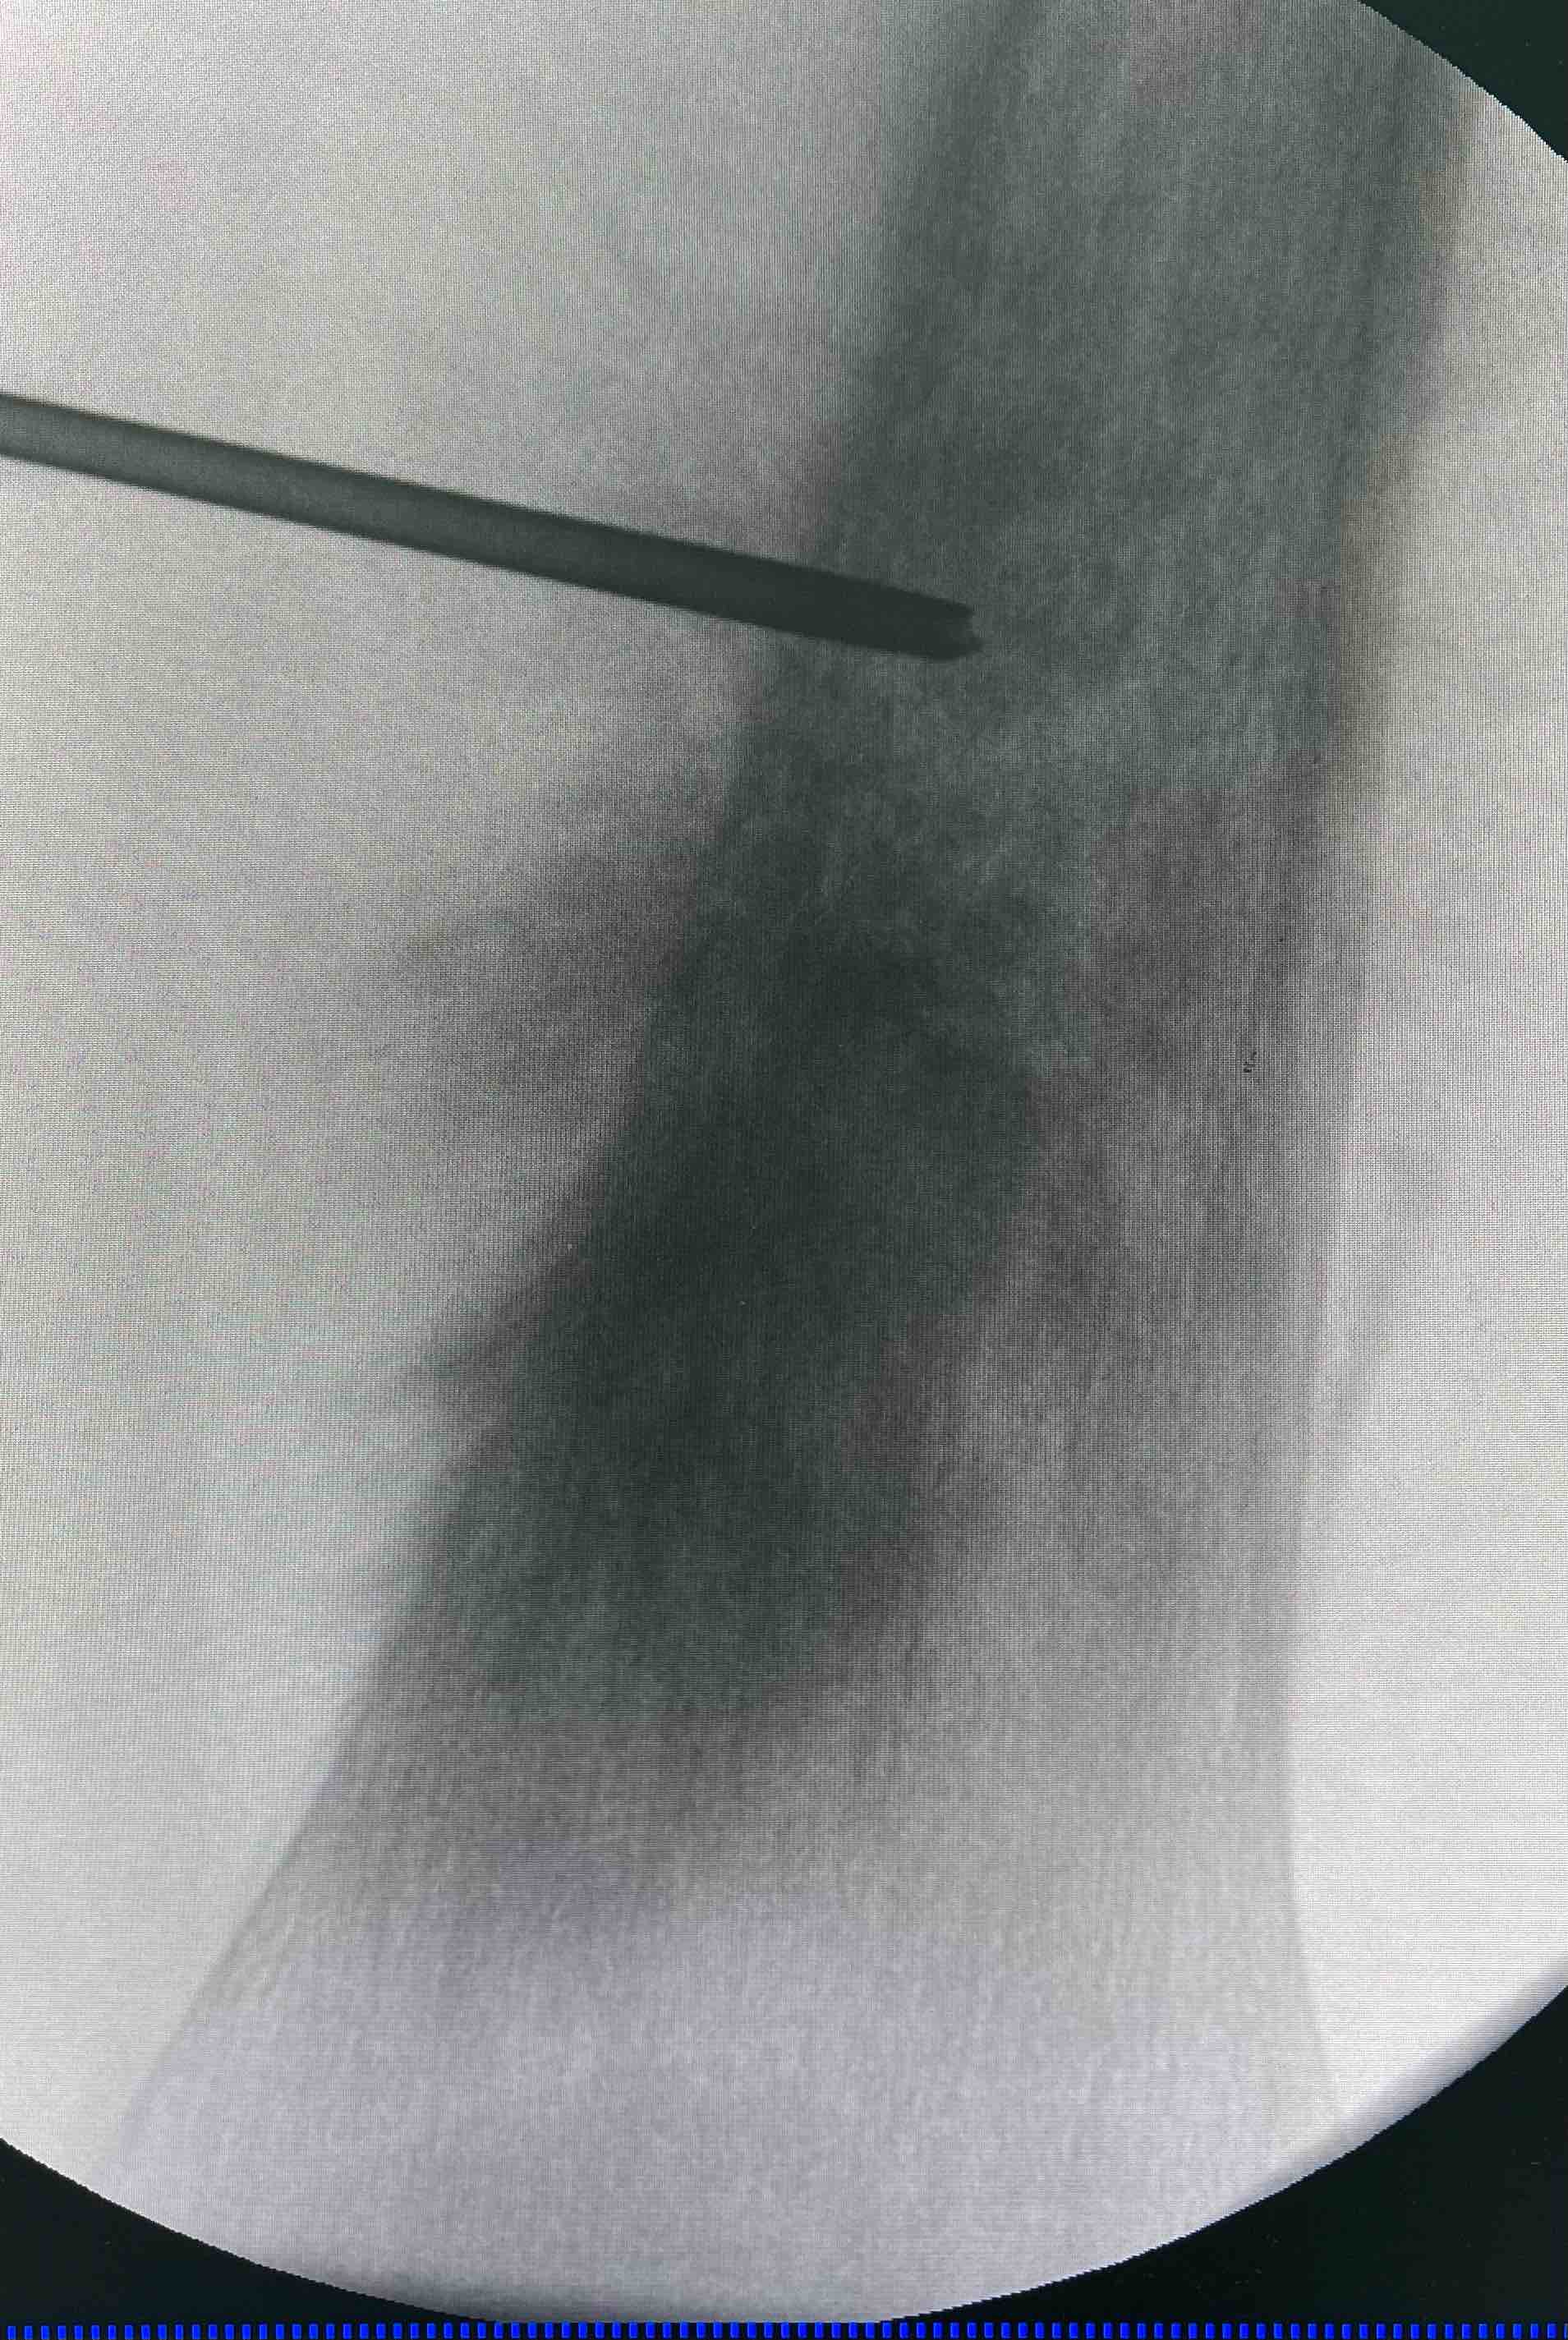

2.其次,活检的意义:第一、活检的首要目的是确诊,我们都知道骨肿瘤的诊断,病理是金标准,但是确诊需要临床➕影像➕病理三结合。由此,活检病理是确诊的关键环节,必不可少。第二、从上述的分型就可以看出,不一样的分型、恶性程度不一致,那治疗方案就会有差异,也就是所谓的个体化治疗。所以,活检确诊分型、给治疗提供依据。第三、很专业的、最重要一条意义,骨肉瘤行新辅助化疗、再手术、手术后辅助化疗。活检病理可作为新辅助➕手术后病理的参照依据,和坏死率评价的一个依据。第四、活检避免了过度手术和非计划再手术的发生,以及误诊和漏诊的风险!

最后,骨肿瘤的活检、尤其是恶性骨肿瘤的活检,一定是规范的、有经验的医生进行操作,避免为二次手术带来麻烦!